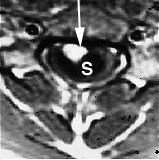

MRI image shows spinal bleeding (myelomalacia).

There are two tests that can provide a definite diagnosis of myelomalacia; magnetic resonance imaging (MRI), or myelography.[8] Diffuse hyperintensity on T2-weighted imaging, and hypointensity on T1-weighted imaging of the spinal cord can be an indication of the onset or progression of myelomalacia